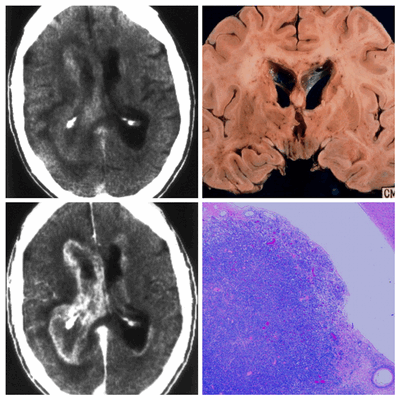

Схематично представлены 2 типа перивентрикулярного паттерна контрастирования

1 тип — утолщённый — справа. Данный тип более характерен для неопластических процессов таких, как лимфома ЦНС и высоко дифференцированная астроцитома.

2 тип — узкий (ширина менее 2 мм) — слева. Данный тип более характерен для инфекционных поражений.

Лимфома ЦНС — это заболевание, которое чаще встречается у ВИЧ-инфицированных пациентов. Изменения при лимфоме ЦНС чаще интрааксиальные, в то время как при вторичном поражении головного мозга (метастазировании) в патологический процесс вовлекаются оболочки головного мозга. Патологические изменения при лимфоме ЦНС, помимо перивентрикулярного накопления контраста, включают в себя солитарный или множественные очаги в головном мозге. Перивентрикулярный паттерн контрастирования является типичным изменением при лимфоме ЦНС, но не патогномичным так, как в большинстве случаев данного заболевания также поражаются мозолистое тело, таламус, базальных ганглии или перивентрикулярное белое вещество.

Ниже представлен коллаж снимков ВИЧ-инфицированного пациента с лимфомой ЦНС.

На аксиальном нативном КТ изображении хорошо определяются патологические изменения в перивентрикулярной области с вазогенным отеком. На постконтрастных изображениях патологические гиперденсные изменения визуализируются больше справа, чем слева. На макропрепарате определяется лимфацитарная инфильтрация вокруг фронтальных рогов. На МРТ на Т1-взвешенных изображениях у пациентов с лимфомой изменения дают от гипо- до изоинтенсивного сигнала, а на Т2 от изо- до гиперинтенсивного сигнала.

Узкий паттерн перивентрикулярного контрастирования более характерен для инфекционных поражений таких, как цитомегаловирусный эпендиматит. На ниже представленных МР Т1 постконтрастных изображениях визуализируется двухсторонний узкий (1 мм) перивентрикулярный паттерн контрастирования у пациента с цитомегаловирусной инфекцией.